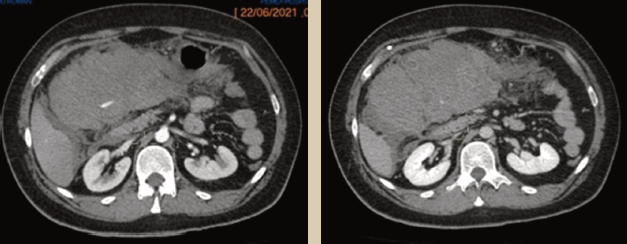

Con estos hallazgos se decidió realizar tomografía simple y contrastada de abdomen, en la que se identificó tumoración en epigastrio, extendida a hipocondrio y flanco derechos, hipodensa, ovoidea, de bordes lobulados, con atenuación en fase simple de 38 UH. Al paso del medio de contraste mostró realce de hasta 59 UH en fase arterial, que se mantuvo en fase venosa, con presencia de vaso nutricio (neovaso), así como zonas compatibles con sangrado (figuras 3a y 3b).

Imagen: Argüello Ramírez et al.

Figura 3a y 3b Tomografía axial de abdomen con contraste intravenoso en fase arterial (izquierda) y venosa portal (derecha), donde se identifica tumoración hipodensa, con zonas de mayor densidad en su interior (flecha), que presenta mínimo realce al contraste, localizada a nivel mesentérico (estrella).